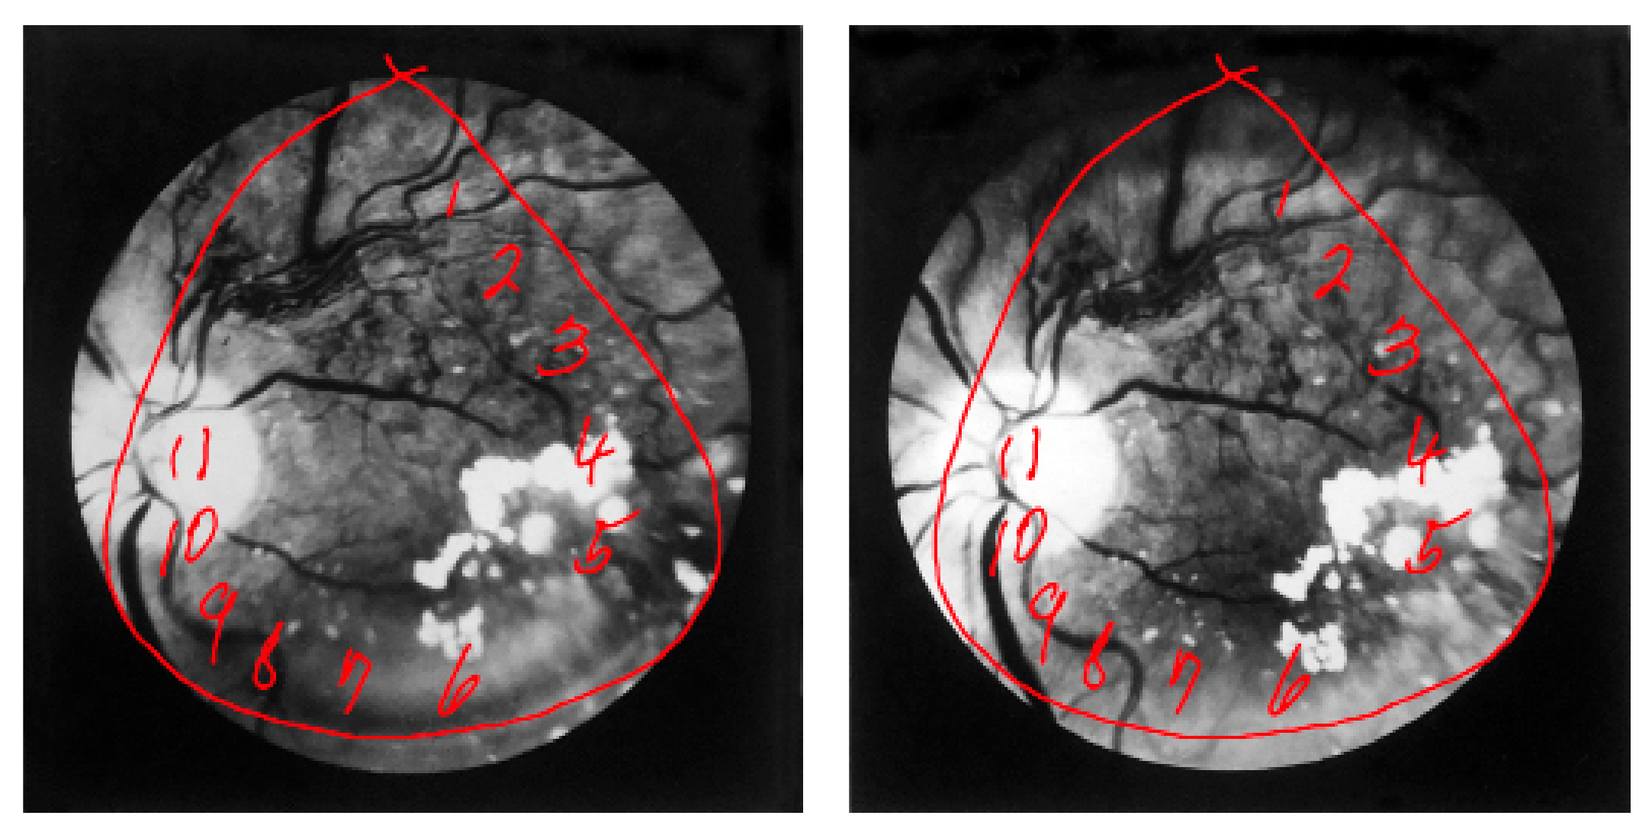

The central premise of this doctoral project is that the progressive cognitive ambiguity that is dementia can be creatively apprehended by way of lostness. As defined by Rebecca Solnit, ‘lost’ holds “...two disparate meanings. Losing things is about the familiar falling away, getting lost is about the unfamiliar appearing.” The initial hypothesis of this research was that in certain neurodegenerative conditions the familiar and unfamiliar can confoundingly combine, and that it’s through the lens of this particular combination that some comprehension of dementia as lived experience may be approached. The disorienting misperceptions most commonly encountered in cognitive decline are visual in nature. Given, then, that dementia reveals the importance of vision to perception, how may the photographic, with lostness as optic, be used to illuminate cognitive decline? In what ways can creatively visualising aspects of neurodegeneration in dementia inform understandings of its existential ambiguities?